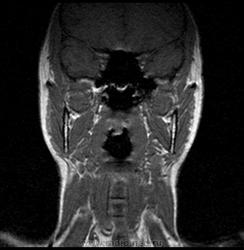

06.06.2011 МРТ - головы и шеи.

Пацентка 36 лет, с жалобами на припухлось в околоушной области справа.

В глубокой доле  правой околоушной железы  на фоне неизмененной паренхимы зона  гетерогенного по Т2, гипоинтенсивного по Т1  с единичными гиперинтенсивными включениями.При контрастировании- накопление контраста диффузное неоднородное и по периферии.Рискну предположить злокачественное образование ( аденокарцинома) с низкой степенью злокачественности( есть капсула, экспансивный рост).Сильно не расстреливайте.

Проблема в том, что перед челюстно-лицевым хирургом стоит распространенность любого объемного процесса, в данном случае все упирается в возмможную травму лицевого нерва и конечно же с дальнейшим его парезом, а ведь женщина  еще молодая. Образование имеет тонкостенную оболочку, по структуре неоднородно, с наличием кальцината, при этом МР-сигнал от окружающих анатомических структур(как костных так и мышечных) не изменен, т.е. об инфильтративном росте речи не идет, в какой то степени доброкачественное. В конкретном случае лицевой нерв с ретромандибулярной веной просто несколько оттеснен.

По гистологии аденома околоушной слюнной железы, но после удаления пока сохраняется парез лицевой мускулатуры, возможно временный.